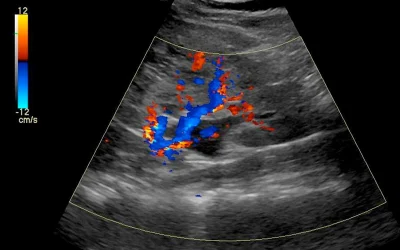

سونوگرافی کلیه در چه مواردی کاربرد دارد؟

سونوگرافی کلیه در چه مواردی کاربرد دارد؟ سونوگرافی کلیه یک تکنیک تصویربرداری پزشکی غیر تهاجمی است که برای ارزیابی کلیه ها و ساختارهای اطراف آن استفاده میشود. این یک...